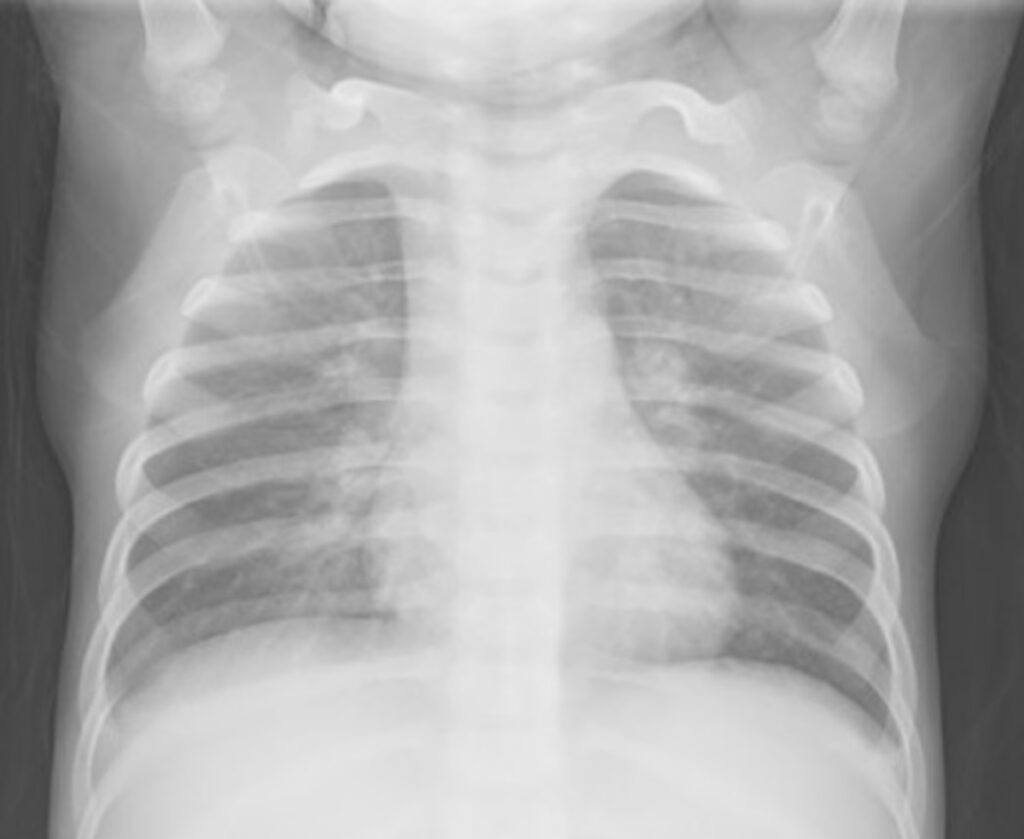

Røntgenbillede af brystet: Et røntgenbillede kan hjælpe med at bekræfte lungebetændelse. Fundene er ofte diffuse og plettede (interstitielle infiltrater), i modsætning til den mere afgrænsede lungebetændelse, man ser ved pneumokokker. Den danske undersøgelse viste dog, at hele 94% af de børn, der fik taget et røntgenbillede, havde forandringer, hvilket understreger, at infektionen ofte forårsager reel lungebetændelse.